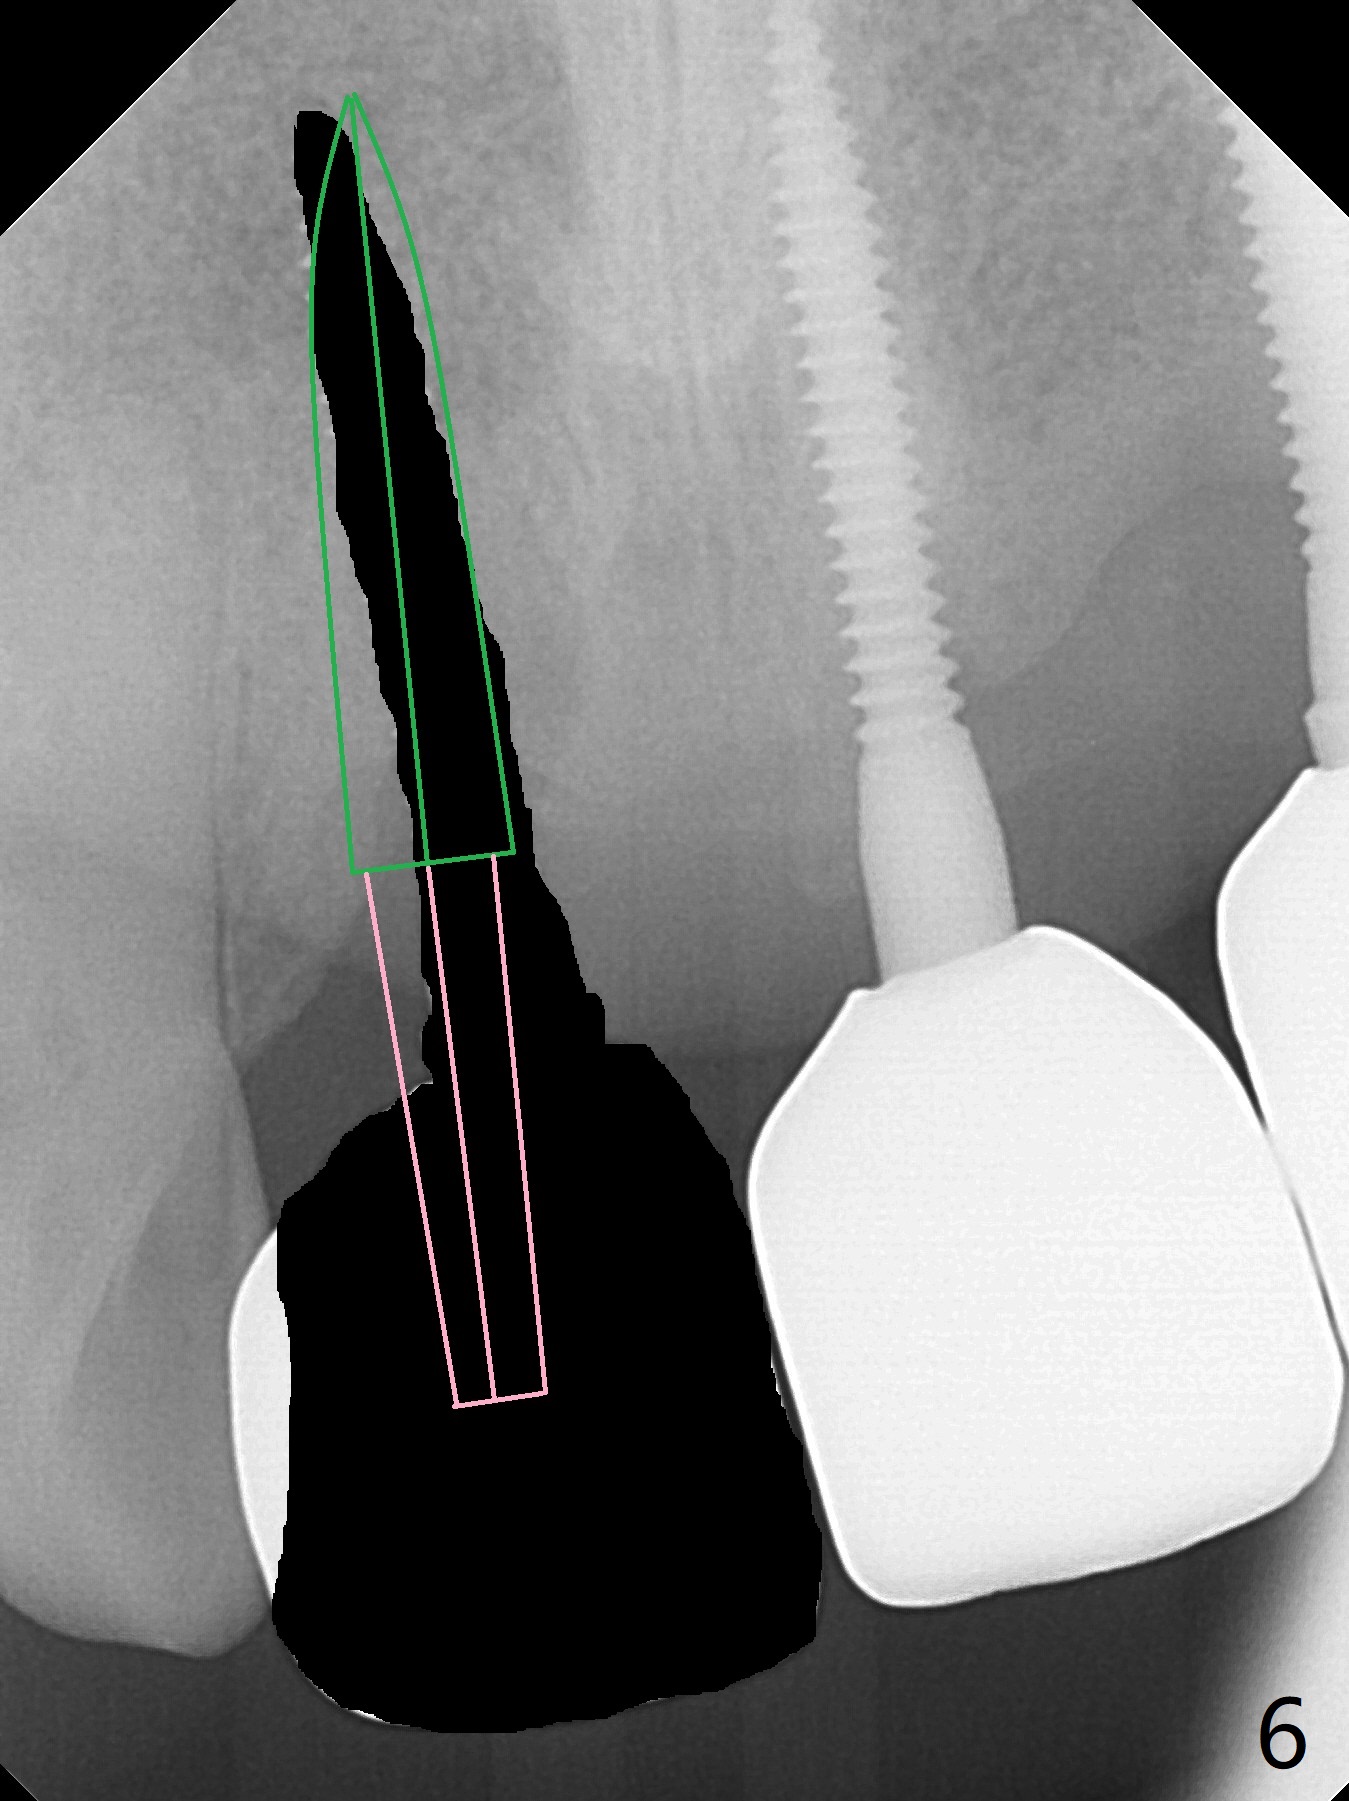

A 43-year-old man has 6 of 1-piece implants in the maxilla (#8-13). His daughter's head hits his upper anterior teeth 7 months post cementation. Exam shows that the tooth #7 has mild percussion. Nine months later the implant crown at #8 becomes displaced and loose when he bites apple (Fig.1 arrow). Forceps are used to remove the crown, leaving a concave implant site (Fig.2). After the crown is bonded to the neighboring tooth/implant crown (Fig.3 *), the patient feels pain from the neighboring tooth. The alveolus is 4.3 mm wide (Fig.4 (2.9 mm preop)), allowing 2.5 or 3.0 mm immediate implant re-placement (Fig.5). A 2.0/3.0 mm trephine bur will be used for implant removal. Try to place the new implant slightly distal to improve the trajectory (Fig.6). Particulate and/or onlay graft is an option. Prepare dummy implants. As planned, the fractured implant is removed by using a 2.0/3.0 mm trephine bur following incision (Fig.7). After use of Lindamann bur to remove the distal bone, a 3x14(4) mm dummy implant is placed with 20 Ncm (Fig.8). A longer implant could be used (3x16(2 or 4) mm), but a 3.5x13 mm 1-piece implant is placed with ~ 50 Ncm after use 3.0 mm drill (Fig.9,10). Allograft is placed around the implant (Fig.9,10 *), followed by Amnion-Chorion membrane and 5-0 PGA sutures (Fig.11). Allograft placed around the implant (Fig.9 *) appears to be able to prevent implant thread exposure 4 months postop (Fig.12). PA is taken when the crown is cemented (Fig.13). Four months postop cementation of #8 crown, the patient returns because of #9 mobility (Fig.14). In fact the implant fractures when the loose crown is removed with forceps; there is bone loss at #10. Bone graft will be placed at #10 with sticky bone (PRFx1), while the implant at #9 is redo. The ridge is wide enough for a 3.5x10 mm implant (Fig.16 (CT taken when #8 implant fractured)). Also prepare Tatum angled 1-piece implant. The 2 mm implant is too thin when occlusion contact at #10-13 is incomplete. The crowns will be redone when the implant at #9 is osteointegrated.